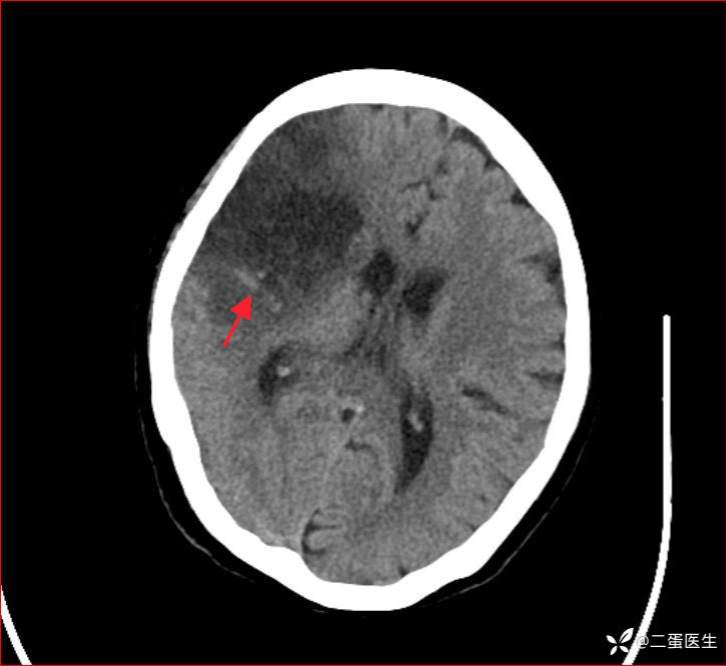

患者溶栓治疗21min时,出现意识改变,Glasgow昏迷评分(GCS)3+4+5,伴失语、左侧偏瘫,左侧上下肢肌力0级,左侧病理征阳性。考虑急性脑卒中,完善头颅CT未见脑出血征象,进一步行头颅CTA提示右侧颈内动脉颈段至大脑中动脉M1段闭塞,缺血性脑卒中诊断明确。

右侧颈内动脉至大脑中动脉闭塞

继续阿替普酶静脉溶栓治疗,并急诊行全麻下脑血管造影+超选择颅内血管腔内取栓术。术中见右侧颈内动脉C4段及以远闭塞(mTICI 0级),取出共5cm黑红色血栓,取栓后右侧颈内动脉完全复流(mTICI 3级)。

术后患者转ICU监护治疗。术后第一天复查头颅CT提示右侧脑梗死伴少许出血转化,在与患者家属充分风险告知后,予依诺肝素0.2ml sc q12h序贯抗凝治疗。